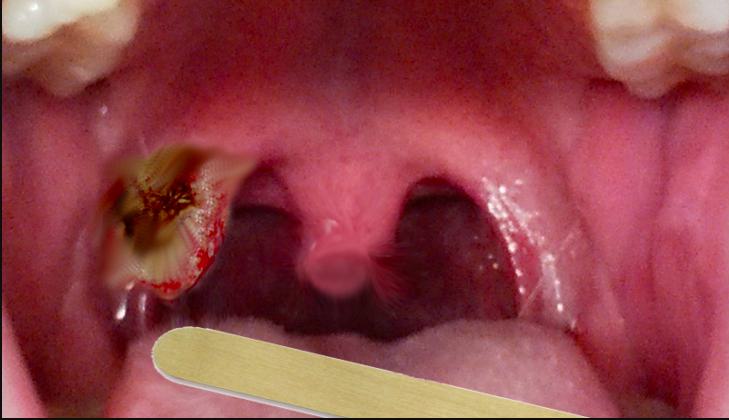

Many people wonder, what does tonsil cancer look like in the mouth? It often appears as a persistent sore, growth, or lump on the tonsil that does not heal. Other symptoms include:

• A visible red or white patch on the tonsil

• One-sided tonsil enlargement

So, what does tonsil cancer look like? It often appears as a persistent sore, growth, or discoloration on the tonsil that doesn’t heal, accompanied by symptoms such as difficulty swallowing and swollen lymph nodes. Understanding the risk factors, symptoms, and treatment options can make a life-saving difference. Early detection remains key, and regular checkups should never be overlooked.

1. What does tonsil cancer look like in the early stages?

It may appear as a small sore, patch, or lump on the tonsil that does not heal, often mistaken for an infection.